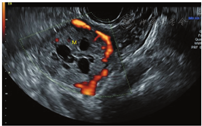

患者女,34岁,于顺产后43 d检查发现右侧卵巢囊实性肿块入院治疗。既往体健,生育史:孕4产2,曾流产2次。妇科查体:子宫正常大小,活动可,于右侧附件区可扪及一直径约5 cm肿块,活动可,界清,无明显压痛,左侧附件区未扪及明显肿块。辅助检查:CEA、CA199、CA125、AFP、卵巢癌相关抗原均为阴性。经阴道超声示:子宫体积正常(三径和约142 mm,宫颈厚28 mm,内膜厚约5.0 mm),宫壁未见明显肿块占位;右侧卵巢体积大、内可见一大小约49 mm×41 mm×39 mm的囊实性肿块,肿块边界清楚,形态规则,内部回声不均匀,可见多个囊性无回声区(较大者约13 mm×11 mm)(图1),能量多普勒示肿块内部及周边可见点条状血流信号(图2),脉冲多普勒(PW)示最高流速(Vmax)0.18 m/s,最低流速(Vmin)0.09 m/s,阻力指数(RI)0.50;子宫及左侧附件区未见明显异常回声。超声提示:①右侧卵巢内囊实性肿块;②子宫及左侧卵巢未见明显异常。进一步行超声造影成像示:增强早期时,右侧卵巢内肿块周边呈环状高增强,并早于子宫肌层增强(图3);内部实性部分呈不均匀等增强,并与子宫肌层同步增强;内部囊性部分无增强(图4)。造影剂消退时,肿块内部早于子宫肌层消退,而周边仍呈环状增强(图5),超声造影提示右卵巢肿块血供较丰富,表现"快进快退"。磁共振增强扫描提示:子宫右上方占位,考虑来源右卵巢性索间质肿瘤-颗粒细胞瘤可能,其他待排。术前拟诊"盆腔肿块性质待查",予行腹腔镜下右侧附件切除术,术中所见:右侧卵巢内见一肿瘤,直径约5 cm,呈囊实性,表面包膜完整,右侧输卵管攀附其上,外观正常;子宫正常大小,左侧卵巢及输卵管外观正常。术后病理镜下见肿瘤细胞弥漫性增生,呈片状、条索状,灶性腺样结构,部分区域可见大小不等的囊腔,核大小较一致,圆形或椭圆形,核仁可见,核分裂象约1~2个/10HPF,间质纤维组织及厚壁血管增生,黏液样变、灶性出血。免疫组化结果显示:Vimentin(+),CD10(+),ER(-),PR(-),CD34(血管+),EMA(-),P53(散在弱+),Ki67(灶性15%+)(图6)。结合免疫组化考虑卵巢性索-间质肿瘤,倾向卵巢间质瘤,送至复旦大学妇产医院会诊,诊断为右侧卵巢微囊性间质瘤。

卵巢MCST形态学表现上有完整的包膜,且实性肿块内部有特征性的微囊结构,这些在二维超声图像上有相应的表现,如本例患者卵巢MCST经阴道超声表现为卵巢内囊实性肿块,肿块边缘可见少量正常卵巢组织并与卵巢界线清楚,肿块边界清楚,形态规则,中央部可见多个规则的囊性无回声区(长径约10 mm)、透声好。彩色血流示肿块周边可见半环形血流信号,内部可见少许点状血流信号显示,频谱多谱勒显示为中等阻力。超声造影增强早期表现为包膜最先呈环状高增强(始增时间早于宫体),内部与宫体同步等增强,并由周围向中心增强,消退期表现为内部早于子宫肌层消退,而包膜仍呈环状持续高增强。